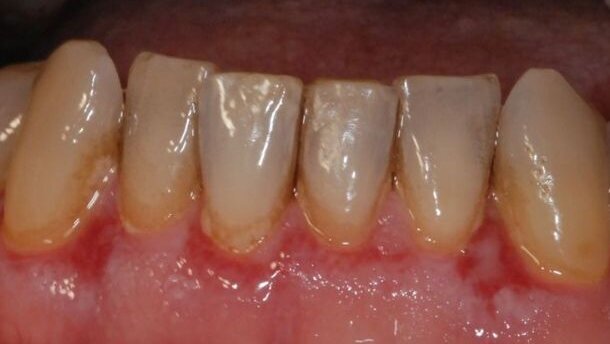

Een patiënt hoeft niet eens klachten te hebben, terwijl het resorptieproces al aan de gang is. Dat maakt ook dat je er niet naar op zoek gaat. Cervicale wortelresorptie wordt vaak per toeval ontdekt: je maakt een bitewing om te controleren op cariës en ziet een vaag vlekje bij een element. Maar omdat je op zoek bent naar gaatjes, kijk je er makkelijker overheen. Een tijd later maak je weer een foto en dan is die vlek veel groter: wortelresorptie. Terugkijkend constateer je dat je het eerder op had kunnen merken. Het is belangrijk om daar alert op te zijn.